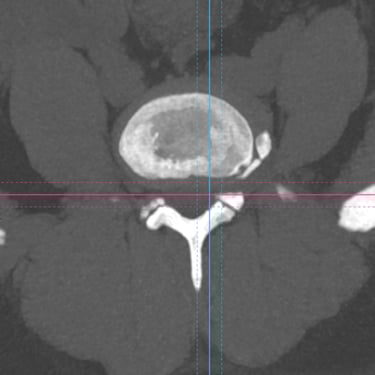

Listesis Lumbar L5–S1 por Fractura Ístmica: Estabilización con FTP y TLIF

La listesis lumbar L5–S1 por fractura ístmica se produce por un defecto en la pars interarticularis que genera inestabilidad vertebral, dolor lumbar crónico y compromiso radicular. Cuando el tratamiento conservador no es efectivo, la artrodesis lumbar con fijación transpedicular (FTP) asociada a la fusión intersomática transforaminal (TLIF) es una alternativa quirúrgica eficaz. Este procedimiento permite descomprimir las raíces nerviosas, restaurar la alineación vertebral y lograr una fijación sólida del segmento afectado. La combinación de estabilización y fusión reduce el dolor, mejora la función y favorece una recuperación segura y progresiva.